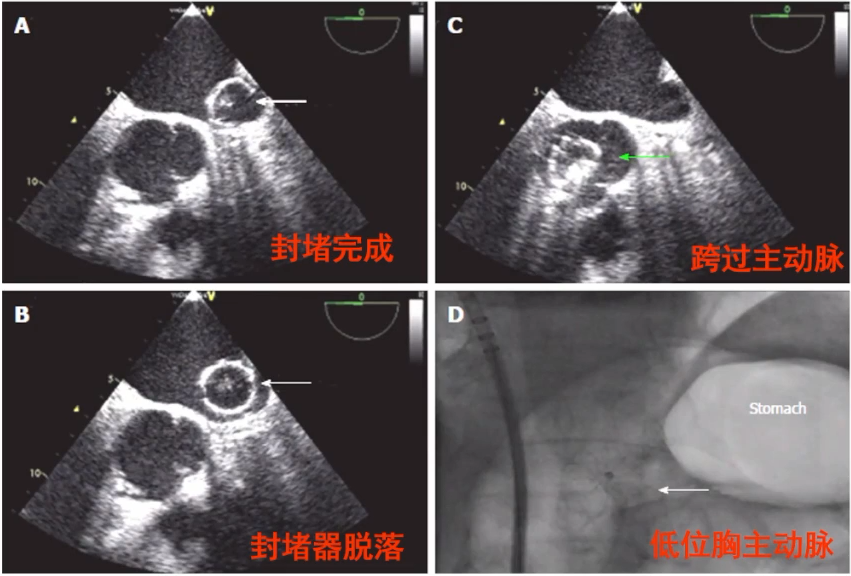

封堵器脱落/移位

封堵器脱落/移位是左心耳封堵术不常见但十分棘手的并发症,Protect AF研究中发生率为0.2%;NCDR研究中发生率为0.07%。

封堵器脱落/移位的防治要点为:

1)根据左心耳形态选择合适的封堵器(至关重要);

2)封堵器大小应合适,避免过小;

3)确保良好的封堵器同轴性;

4)术后行TTE明确有无封堵器脱落/移位;

5)封堵器脱落至左房或主动脉内,通常可经皮介入取出;

6)封堵器脱落至左室内,通常需外科手术取出。

封堵器脱落后经皮介入取出

一项实验性封堵器脱落后处理研究显示,脱落部位位于左心房/主动脉时,抓捕成功率为100%,但如果落于左心室,抓捕封堵器成功率较低,且可能造成较严重的瓣膜损伤。